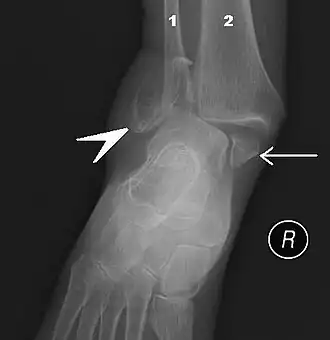

![]() Правый голеностопный сустав, вид сбоку. | |

Методика исследования

В ходе объективного обследования применяются физикальные методы исследования: осмотр, пальпация. Немаловажное значение имеет тщательный сбор анамнеза. Из инструментальных методов большое распространение получило рентгенологическое исследование голеностопного сустава в прямой, боковой, а также косой проекции. В настоящее время для диагностики применяют также артроскопию.